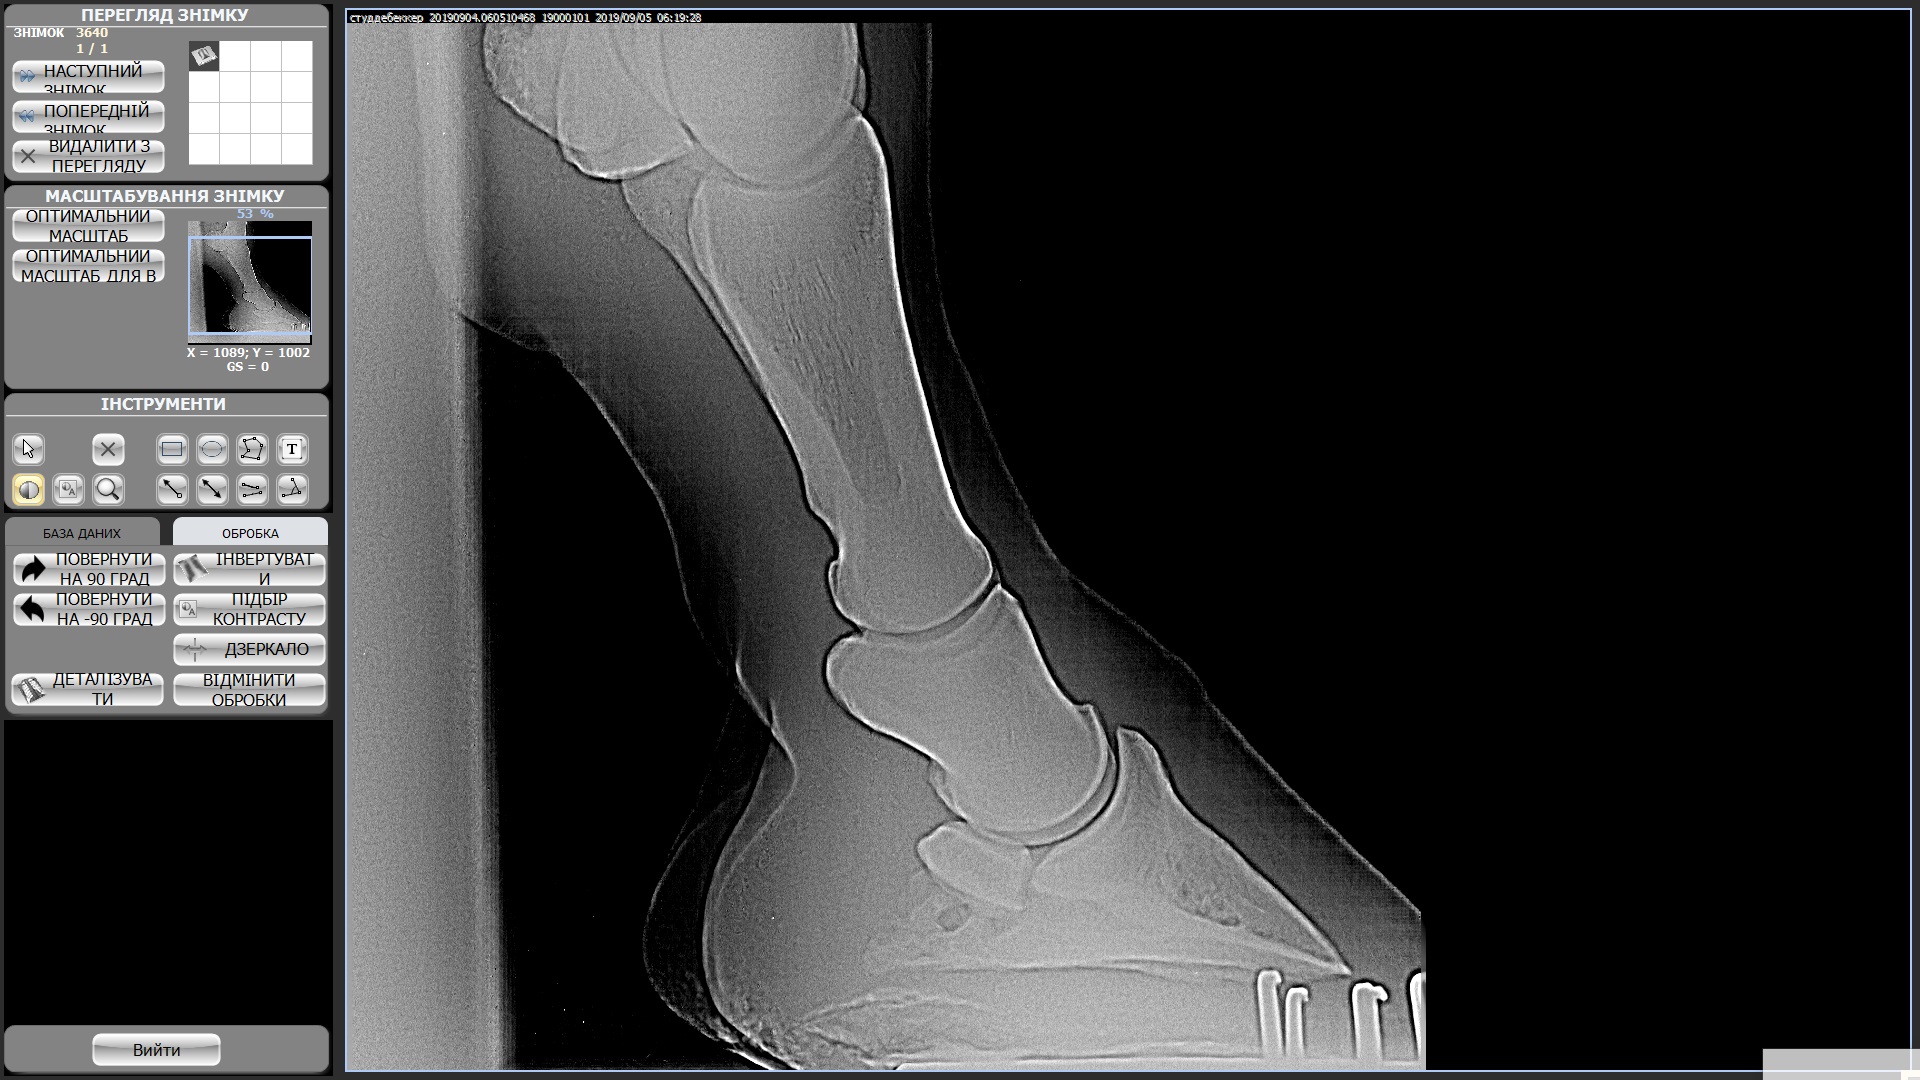

Мерин 7 лет, купили в этом году, смотрели с ветом и делали рентгены ног, прикрепила к теме. Были микротравмы суставов из за чего появляются наливы (мягкие шишки) на суставах всех 4х ног. Приглашала другого вета сказал менять постав подковами ортопедическими, так и сделали после чего конь захромал на правый перед и оба зада, проходили так неделю и сняли подковы - хромота ушла, но копытные остались налитыми, как и шишки не сошли. Вроде бы все было хорошо на протяжении 2х недель, наливы не сошли, но конь на них не жалуется. И вот на днях ходили в поля (только шагом), пару раз нас напугала то машина, то веточка и он подрывался немного. На следующее утро хромает на все 4, щупали мышцы и смотрели наливы изменений нет но конь хромает на все 4 и немного теплые копытные((((

Студдебекер 3 ЗЛ.jpg494 KB · Просмотры: 366 -

студебеккер 2 ЗП.jpg404.4 KB · Просмотры: 370 -

СтудебеккерПЛ.jpg489.8 KB · Просмотры: 327 -

Студебеккер ПП.jpg528.2 KB · Просмотры: 411 -